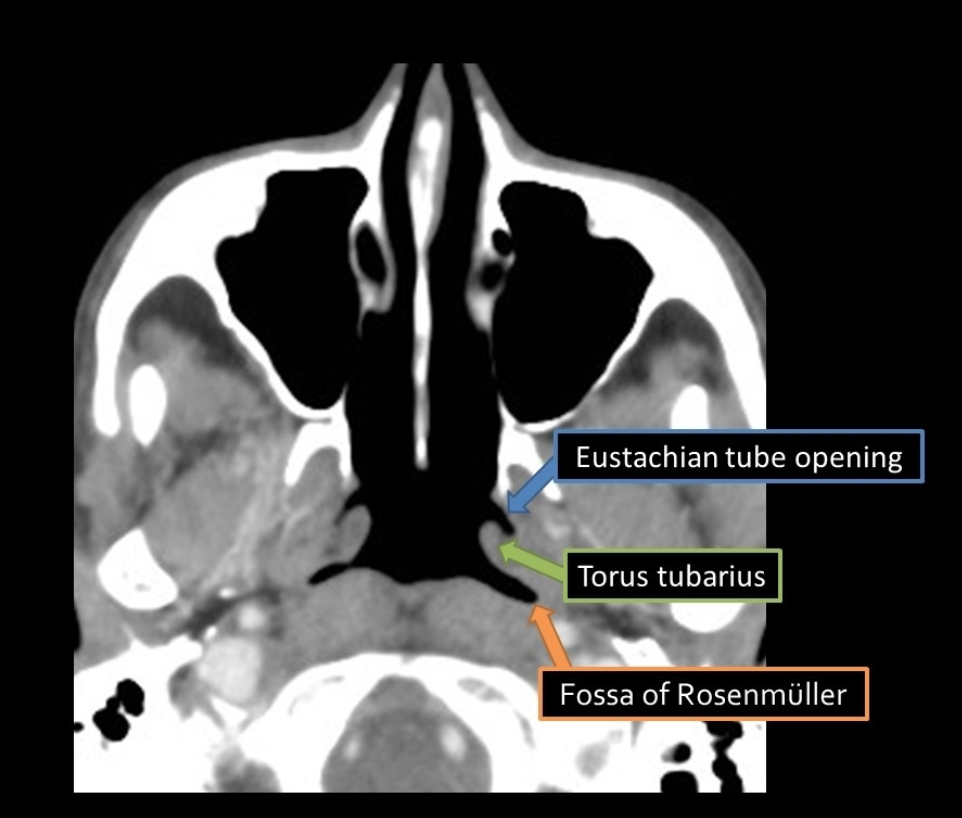

Fossa of Rosenmuller

• Aka posterior-lateral pharyngeal recess

• Most common site for nasopharyngeal carcinoma

Case courtesy of Hoe Han Guan, Radiopaedia.org, rID: 150887